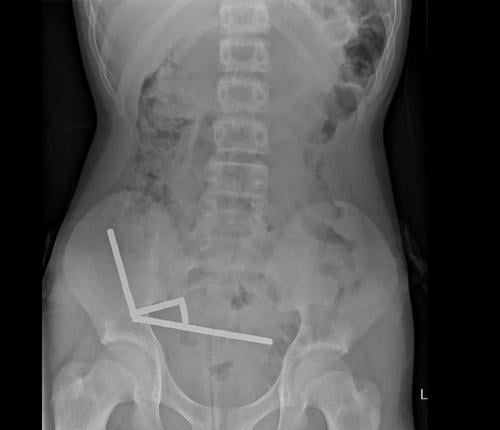

X光显示,这些磁铁在肠道内连成4条直线,形成强大压力,导致小肠和盲肠四处坏死。医生最终成功手术取出所有磁铁,男童在住院8天后出院。